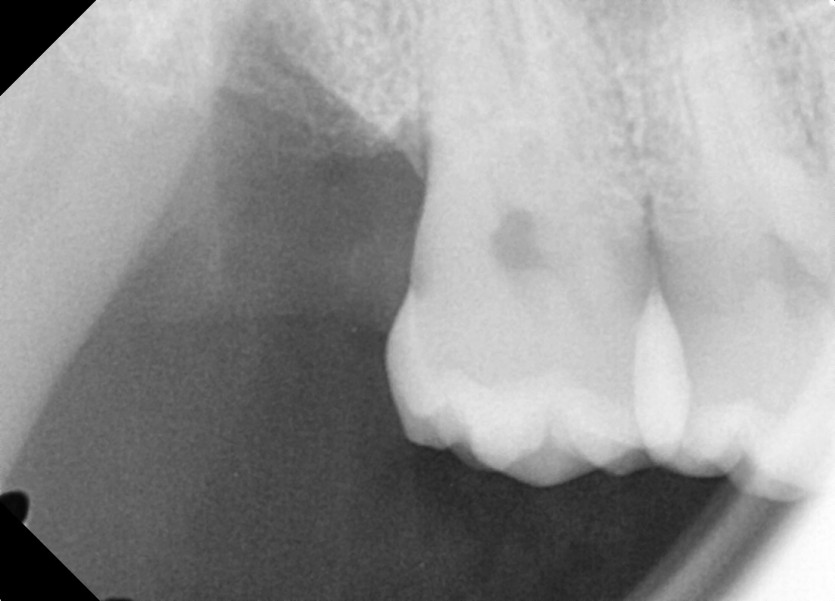

#18,48 사랑니 발치

구강 외과 전문의가 당일 발치했습니다.